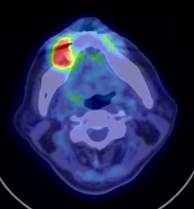

18F alpha-methyl tyrosine(18F-FAMT)は、サイクロトロンで合成される18Fにより標識されたタイロシンと類似の挙動を示すPET用アミノ酸製剤で、PETカメラを用いて画像化されます。18F-FAMTは、癌細胞で特異的に発現しているアミノ酸の輸送担体であるLAT1を介して癌細胞内に取り込まれるため、LAT1を発現する癌細胞の画像化が可能となります。1998年、群馬大学で井上、富吉らにより開発され、現在は臨床研究として年間約300件の検査が行われています。PET検査で頻用されるブドウ糖製剤のFDGと異なり、炎症には集積しないため、より特異性の高い腫瘍の診断が可能です。口腔外科、呼吸器外科、脳神経外科などと共同研究が進行中です。

結果の一部は論文として発表されています。